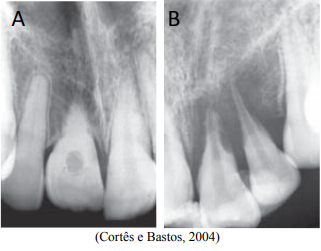

Analise as imagens a seguir.

As reabsorções radiculares representam umas das principais complicações pós-traumatismo do processo de reparo das estruturas de sustentação, podendo levar, muitas vezes, à perda do dente. As imagens radiográficas das ilustrações A e B sugerem alterações radiculares, respectivamente, de